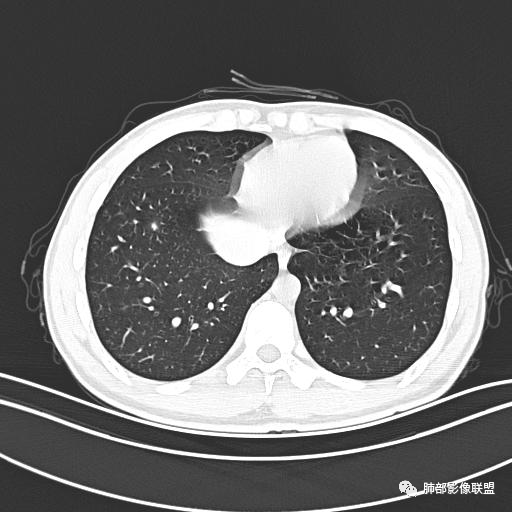

男,19岁

主  诉:发热、全身皮疹2天。

现病史:患者源于2天前受凉后出现发热,最高体温为38.5℃,且颜面部出现少量皮疹,无鼻塞、流涕、咳嗽、咳痰,未在意而未作特殊处理,次日全身皮疹逐渐增多至全身,伴轻度瘙痒,在当地卫生所给予抗病毒、抗感染治疗(具体用药不详)体温有所下降,但皮疹无明显消退,无腹痛、头痛,食欲无明显减退,为进一步诊治,遂于今日急来我院求治,患者目前精神尚可,体力正常,食欲正常,睡眠正常,体重无明显变化,大便正常,排尿正常。

小强:青年,发热,皮疹;双肺散在结节,周围磨玻璃,点晕征,疱疹病毒感染,鉴别荚膜组织胞浆菌,结核。 大雄:青年,急性起病,发热伴全身皮疹2天,抗病毒治疗体温有下降。双肺随机分布大小不等类圆结节,“点晕征”。考虑水痘-疱疹病毒(VZV)血播询问接触史,查体皮疹分布以及形态基本可诊断。 王开金江津中心医院呼吸科:青年男性,起病急,病程短,以发热,皮疹为首发症状,感染指标以单核细胞升高为主,胸部ct双肺多发结界,周围有晕,点晕表现,随机分布,同意於老师意见,水痘疱疹病毒血流感染累及肺。 王秀仙:双肺多发大小不等结节,周围有晕,边缘模糊,呈点晕征表现。青年,急性起病,发热伴全身皮疹2天,抗病毒治疗体温有下降。考虑疱疹病毒。鉴别荚膜组织胞浆菌。 傅昌瑜:19岁男性,发热、全身皮疹2天,单核细胞增高,双肺多发结节,结节边缘见边界不清磨玻璃影。点晕征+发热、全身皮疹+单核细胞增高——考虑水痘-带状疱疹病毒肺炎。 一切∮随缘:年轻男性,发热,皮疹两天,实验室,CRP,PCT增高,影像:双肺多发散在磨玻璃结节,边界欠清,大小不等,呈点晕征改变,以血管束周围分布为主,局部血管束略增粗,其它无明显改变,考虑:1:病毒性肺炎(水痘疱疹病毒?不知道皮肤有无改变)2:真菌(组织胞浆菌,血管侵袭性肺曲霉)3:GPA4:寄生虫(实验室没有看到嗜酸细胞增高) 赵山河:双肺散在结节,周围有晕,边缘模糊,呈点晕征表现。青年,急性起病,发热伴全身皮疹2天,抗病毒治疗体温有下降。考虑水痘—疱疹病毒感染。洪桥爱:青年男性,发热、皮疹2天,伴瘙痒,皮疹于面部首发,之后进展至全身,虽然没有对皮疹进行描述,但是从出疹时间及皮疹进展情况,伴瘙痒,应该就是个水痘患者;CT提示双肺随机分布结节影,部分结节伴有边界不清晕征,考虑水痘血播肺。 刘强:年轻男性,急性起病,皮疹,发热,抗感染治疗体温下降,说明有效。影像表现为散在点晕征,感染类疾病谱(疱疹病毒,真菌,结核),结合年龄,皮肤皮疹,考虑水痘-疱疹病毒性肺炎。 小兜:男性,19岁,发热皮疹两天,颜面部至全身,CRP,降钙素及单核增高。CT示双肺散在小结节,周围伴磨玻璃影,点晕征,考虑为水痘-带状疱疹病毒(varicella-zoster virus,VZV)肺炎 必有路:青年,皮疹+发热+“点晕征”→水痘-疱疹病毒(VZV) 许慧良:青年男性患者,发热、皮疹2天,体温最高38.5℃,第3天皮疹扩展至全身,伴瘙痒,胸部CT:双肺多发随机分布的小结节,结节周边见边界模糊的晕征,考虑水痘病毒感染流心明智:男,19,急性起病,发热伴全身皮疹2天。出疹顺序头→全身,抗病毒有效。胸部CT:两肺多发大小不等类圆形实性小结节影,随机分布,结节周围环绕GGO,边界模糊,呈点晕征。出疹特点是关键,未提示。考虑:血播病毒性肺炎,水痘-疱疹病毒?麻疹?鉴别荚膜组织胞浆菌、TB、血管炎、寄生虫等。 浪迹天涯:病灶多为5-10mm大小结节,结节周围可见磨玻璃样的晕环,常多发,可分布于肺内任何区域,考虑水痘—带状疱疹病肺炎如果短时间内有新的一个区域浸润,更加能说明,